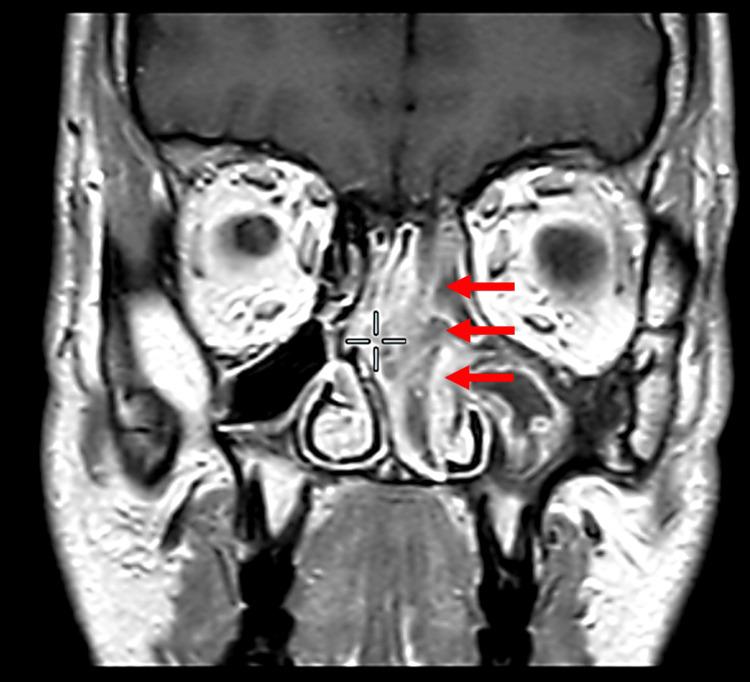

Hamartomas are rare, tumour-forming, benign lesions that have been reported throughout the body that can resemble other malignant entities. Hamartoma subtypes can be distinguished based on their histological features. Sinonasal hamartomas may have presenting symptoms and radiological features that mimic other nasal neoplastic lesions. Therefore, it is essential to diagnose it accurately, as the treatment approaches can range from radical surgeries in malignant cases to a simple excision in hamartoma. In this paper, we report a novel case of sinonasal hamartoma, which demonstrates an unprecedented histological feature of glial tissue with astrocyte-like cells. Furthermore, we present the unconventional presenting symptoms and radiological features seen in this case that mimic the behaviours of nasal inverted papilloma (IP) lesions, thereby highlighting the need for careful investigation of such patients in order to distinguish both glial hamartoma and IP lesions. Concluding that identification of glial hamartoma as a new subtype of sinonasal hamartoma is crucial, as mistaking it for other lesions may subject patients to overly aggressive treatment and potential unnecessary harm.

错构瘤是一种罕见的、形成肿瘤的良性病变,全身各处均有报道,可类似其他恶性病变。错构瘤亚型可根据其组织学特征进行区分。鼻窦错构瘤可能具有与其他鼻腔肿瘤性病变相似的临床表现和影像学特征。因此,准确诊断至关重要,因为治疗方法从恶性病例的根治性手术到错构瘤的简单切除不等。在本文中,我们报告了一例新型鼻窦错构瘤病例,其显示出具有星形胶质细胞样细胞的神经胶质组织这一前所未有的组织学特征。此外,我们展示了该病例中出现的非传统临床表现和影像学特征,这些特征类似于鼻腔内翻性乳头状瘤(IP)病变的表现,从而强调了对此类患者进行仔细检查以区分神经胶质错构瘤和IP病变的必要性。结论是,将神经胶质错构瘤鉴定为鼻窦错构瘤的一种新亚型至关重要,因为将其误诊为其他病变可能会使患者接受过度激进的治疗并可能遭受不必要的伤害。